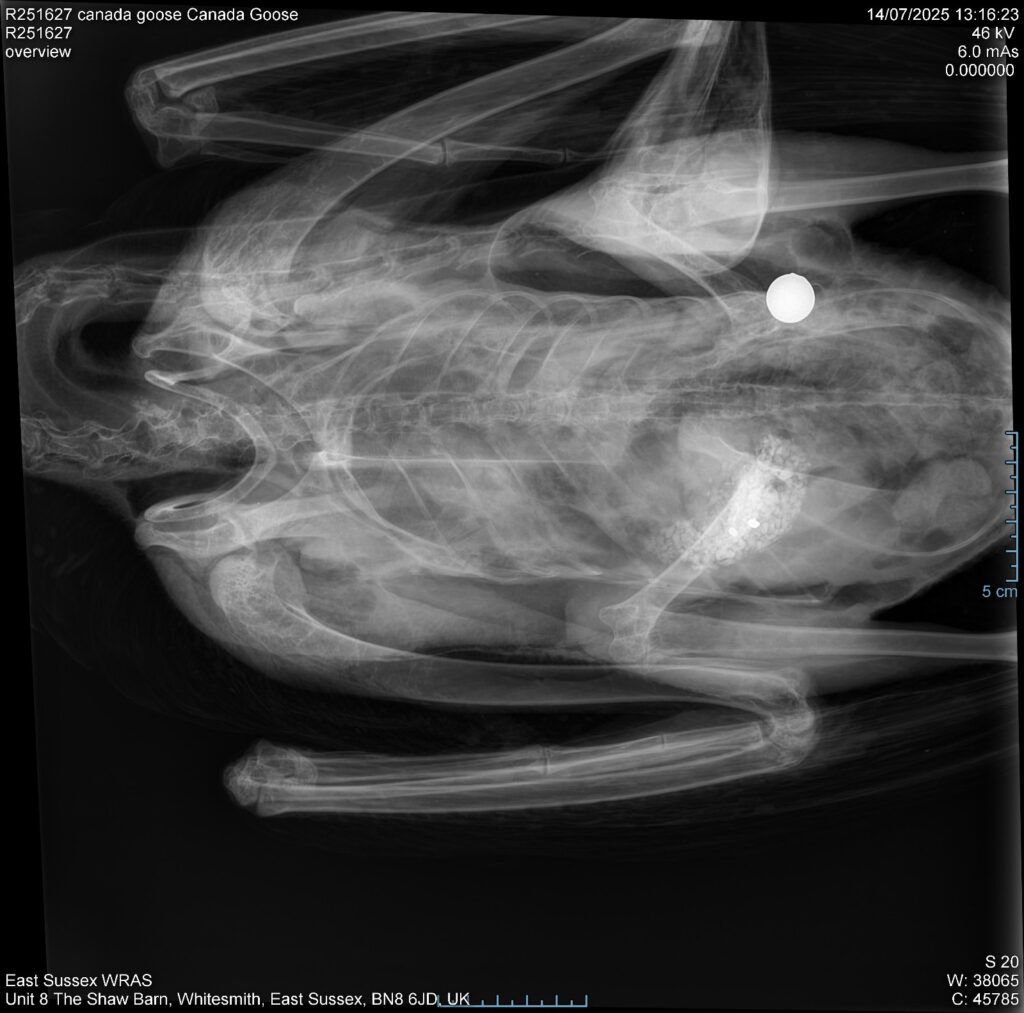

Russ said: “The use of powerful catapults shooting steel ball bearings is inflicting catastrophic injuries and killing waterfowl such as swans, geese, and ducks in our parks and on our waterways.